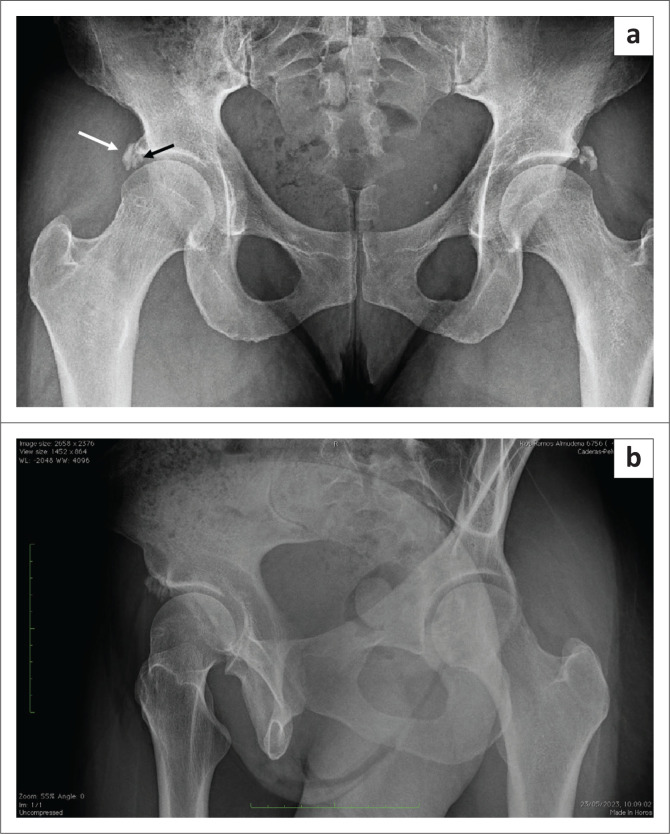

This report describes a rare case in which double calcifications of the acetabular labrum and rectus femoris occurred concomitantly in a middle-aged female patient who was treated successfully with surgical intervention via hip arthroscopy.

Contribution: This case highlights the existence of various types of calcifications around the acetabulum, with a proposed new classification system for acetabular and periacetabular rim ossifications.